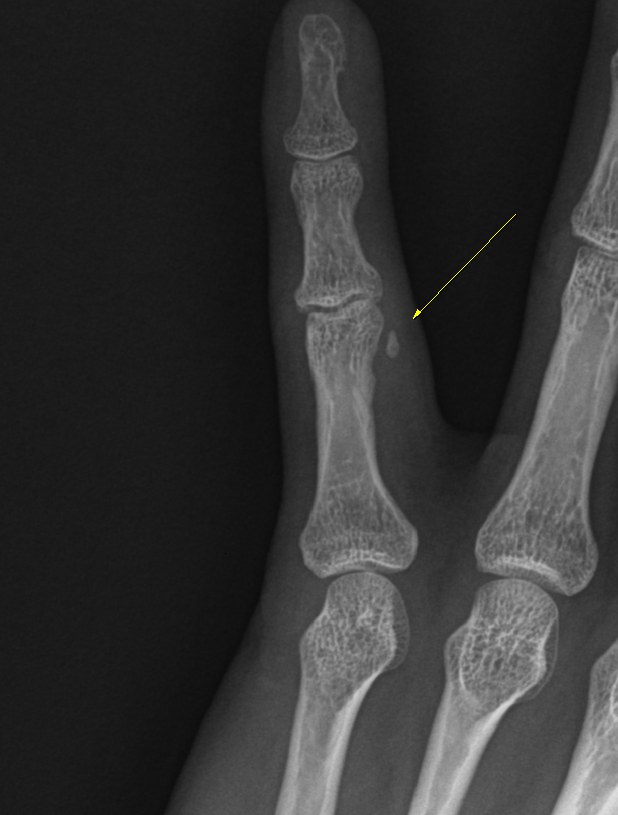

Subject   손가락을 삐엇다고 생각했는데.. 수술해야 할까요?

어제 밤에 얼음꺼내다 냉장고 문에 새끼손가락을 삐엇습니다.

x-ray상에선 작은 뼈조각이 떨어져나간게 보이는데 수술해야 할까요?

건열골절, 근위지골, 그위지관절의 요골촉부위, 5수지, 좌측